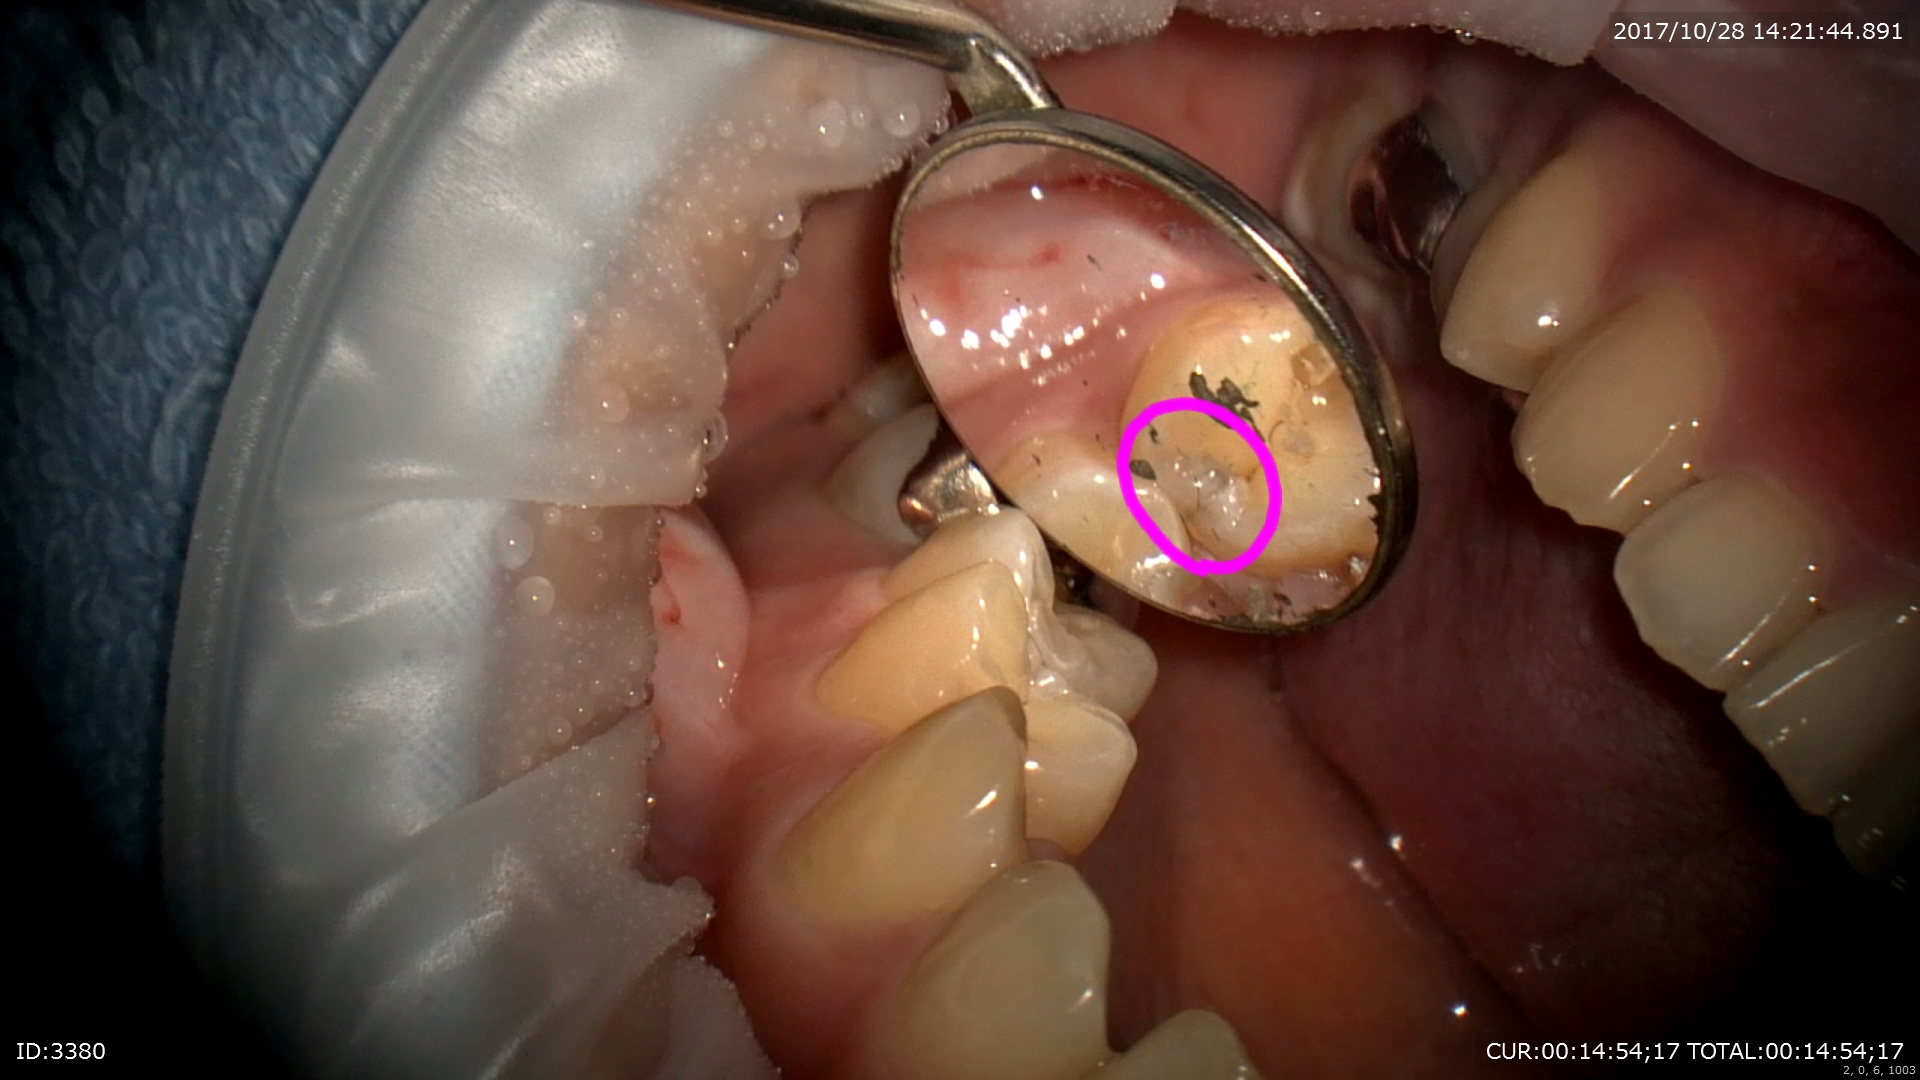

歯と歯の間にむし歯が出来るケースが1番多いのですがその診査の為にマイクロスコープを使用しました。

この丸の部分なんとなく黒く透けていますよね。

上の部分をマイクロスコープ下で無痛で丁寧にとります。

むし歯は内部でこんなに広がっているんですね。

↓むし歯検知液を使うと感染源のみとれるから無駄な歯を削らずに済みます。